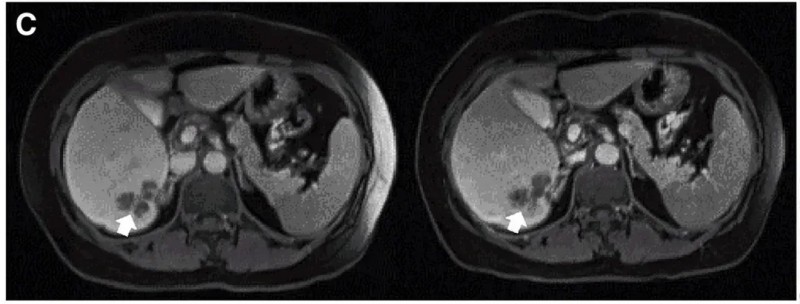

结果振奋人心:10例既往治疗进展(PD)的患者中,7例治疗后达到病情稳定(SD),肿瘤直径仅轻微变化,其中2例稳定状态持续超30周(7.5个月)。值得一提的是,其中一个典型病例(P10患者)在接受DL4剂量CEA CAR-T治疗后,MRI证实其肝内一处病灶明显缩小(详见下图)。

▼P10患者在CAR-T治疗前(左图)、治疗4周后(右图)的MRI对比

▲图源“Molecular Therapy”,版权归原作者所有,如无意中侵犯了知识产权,请联系我们删除